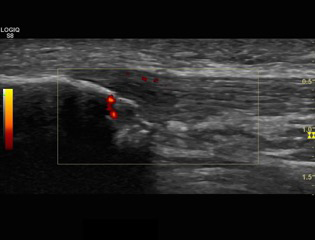

Structural findings of collagen degeneration and angiofibroblastic neoplasia have been well described and are now referred to as "neovascular tendinosis." The presence of neovascularization has been theorized to cause pain in patients with tendinopathy.2 Recent studies have examined the role of neo-vessels and neo-innervations on chronic tendon pain and dysfunction, and interventions targeting this process have reported favorable outcomes in RPT (Figure 1-4).3

Figure 1 Ultrasound image with power Doppler. Longitudinal view of a Patellar neovascular tendinopathy, with thickening of the tendon and hipoecoic image.